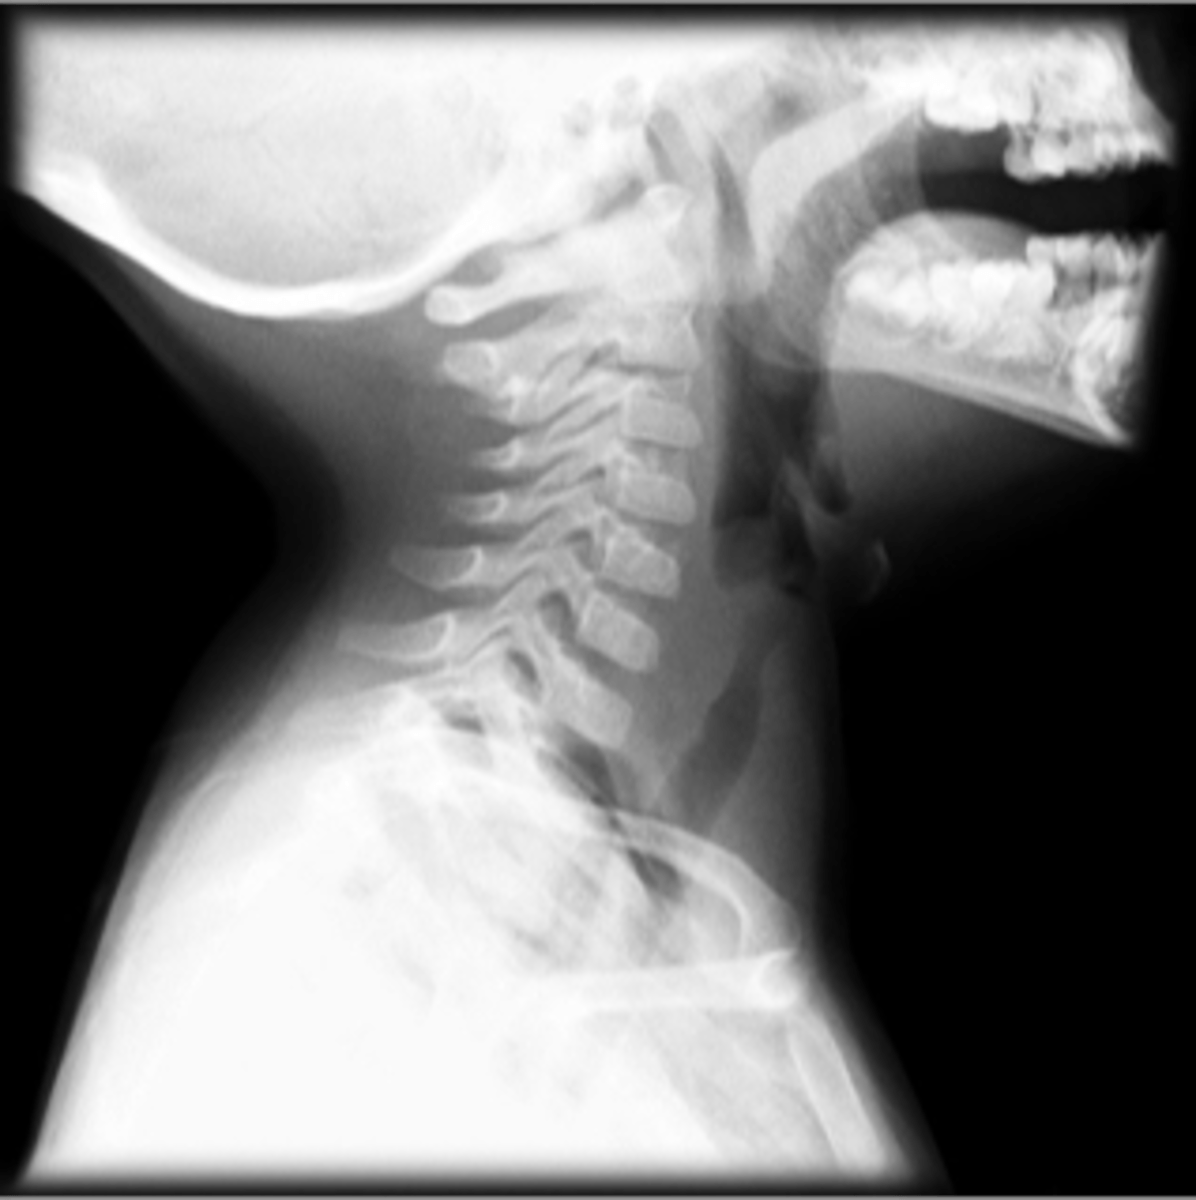

Epiglottitis (thumb sign)

knowt flashcard image